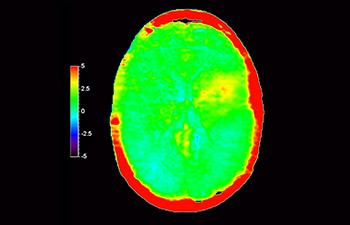

Numa sociedade para a qual os distúrbios neurológicos representam um fardo pesado, a Philips está empenhada em proporcionar uma extraordinária clareza de diagnóstico e orientações de tratamentos para todos os pacientes. Atualmente, embora a RM seja o padrão de excelência no diagnóstico por imagem em neuro-oncologia, sua precisão na classificação de tumores e na avaliação de acompanhamento dos tratamentos pode ser aprimorada. O APT (Amide Proton Transfer) 3D é um método exclusivo de diagnóstico por imagem por RM do cérebro sem contraste que aborda a necessidade de um diagnóstico mais confiante em neuro-oncologia. O APT 3D utiliza a presença de proteínas celulares endógenas para produzir um sinal de RM que se correlaciona diretamente com a proliferação celular, um marcador de atividade tumoral. O APT 3D pode auxiliar profissionais de saúde capacitados na diferenciação entre gliomas de baixo e de alto grau e a diferenciar a progressão tumoral do efeito do tratamento.1

com o APT 3D